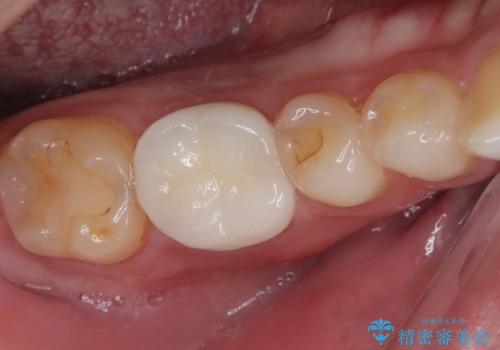

セラミックの詰め物が欠けたのでやり替えたい オールセラミッククラウン